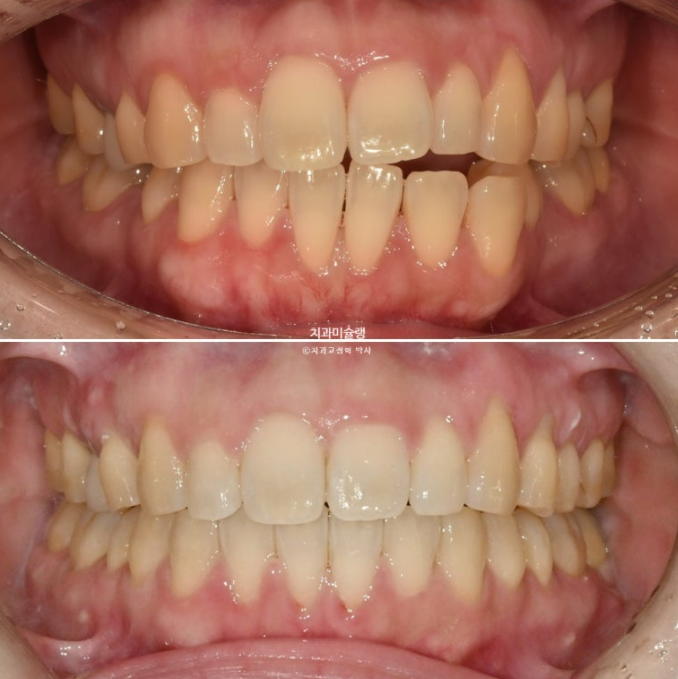

오늘은 30대 환자분의 개방교합 재교정 케이스 소개하겠습니다.

치료방법은 인비절라인 입니다.

24.06~25.11

20년 전 교정을 했는데 재발이 되어 재교정을 위해 온 30대 환자분입니다.

이제 전후비교 보겠습니다.